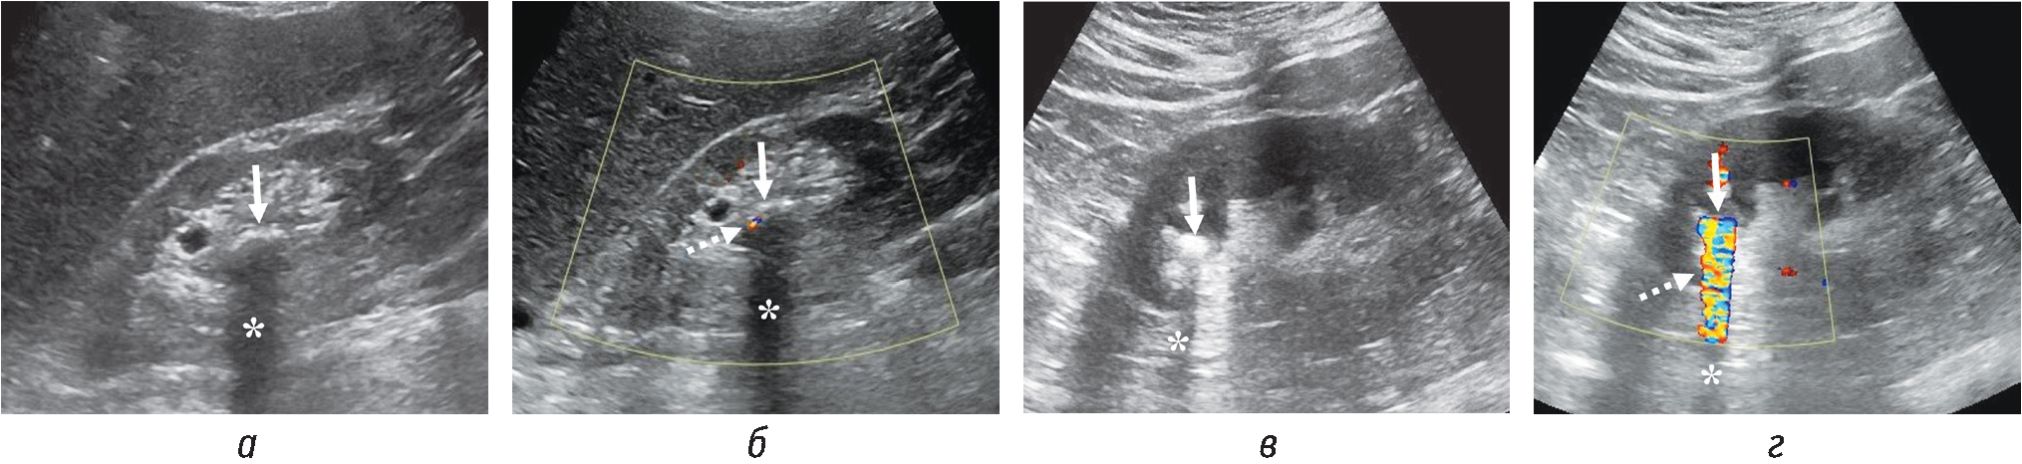

По данным авторов, чувствительность и специфичность феномена АТ в сочетании с АМ (рис. 2) в определении конкремента МВП размером 5 мм и более составляет более 89 % и достигает 100 % в определении конкрементов размером 10 мм и более. Однако для конкрементов размерами 1–3 мм чувствительность и специфичность оказываются низкими: от 50 до 60 % [7].

Рис. 2. Трансабдоминальные сонограммы (а–г) двух пациентов: а — конкремент одного пациента размером 12 мм в нерасширенной лоханке с акустической тенью; в — конкремент другого пациента размером 8 мм в расширенной чашечке с акустической тенью. Конкременты указаны сплошными стрелками, акустическая тень — звездочкой. Соответствующие сонограммы в режиме ЦДК представлены на изображениях б и г. АМ каждого из конкрементов указан пунктирными стрелками